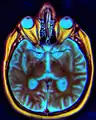

IRM de Chiasma optique.